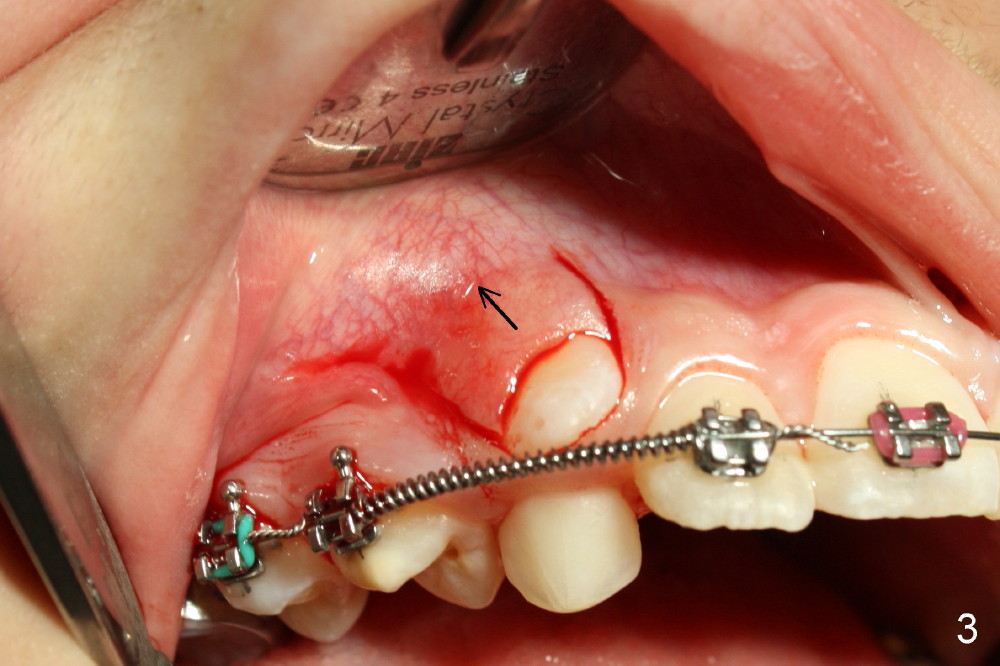

Two oblique incisions were made mesial and distal to UR3 (Fig.3). The mucoperiosteal flap (Fig.3 arrow; Fig.4 F) was raised and pushed apically for bracket placement. Following extraction of UR C, one-fourth inch elastics were placed between U3 and L3,4 (Fig.5,6). The patient was instructed to wear the elastics 24 hours per day. The upper wire is .018 ss with open coil springs, while lower .020.